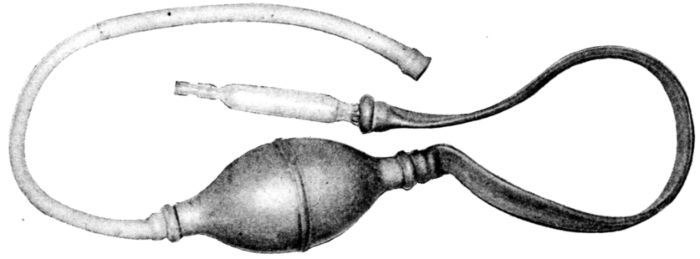

| 115. | Syringe for filling above bags after insertion | 312 |